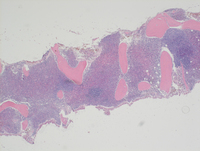

Bone core biopsy Glycophorin-C stain

Additional Glycophorin-C stain highlights the clusters of cells confirming erythroid lineage. Although not shown here, CD34 stain did not show any increase in blasts. CD117 immunostain demonstrated weak staining in the erythroid precursors and in addition highlighted increased numbers of dispersed mast cells throughout the biopsy although large tight mast cell clusters were not present.